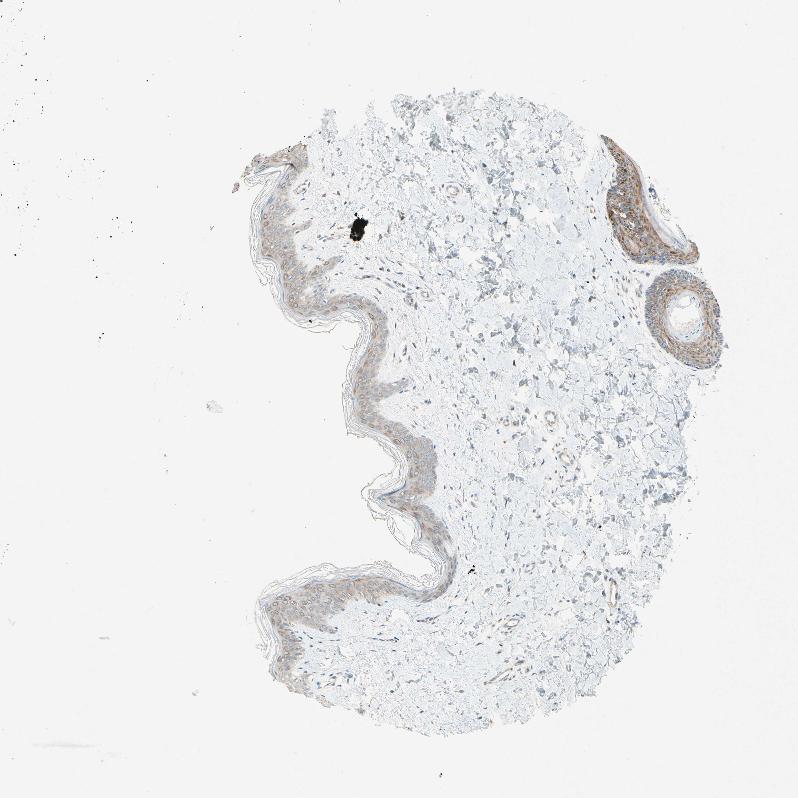

SKIN 1 - Antibody stainingi

Antibody staining in the annotated cell types in the current human tissue is reported as not detected, low, medium, or high, based on conventional immunohistochemistry profiling in selected tissues. This score is based on the combination of the staining intensity and fraction of stained cells.

Each image is clickable and will lead to virtual microscopy that enables deeper exploration of all samples and also displays staining intensity scores, fraction scores and subcellular localization as well as patient and tissue information for each sample.

Antibody HPA045423Antibody CAB011536

SKIN 2 - Antibody stainingi

Cells in basal layer -Medium

Cells in corneal layer -Not detected

Cells in granular layer -Medium

Cells in spinous layer -Medium

Endothelial cells -Low

Epidermal cells Low-

Extracellular matrix -Not detected

Fibrohistiocytic cells -Low

Langerhans cells -Medium

Lymphocytes -Not detected

Melanocytes -Not detected

Vascular mural cells -Not detected